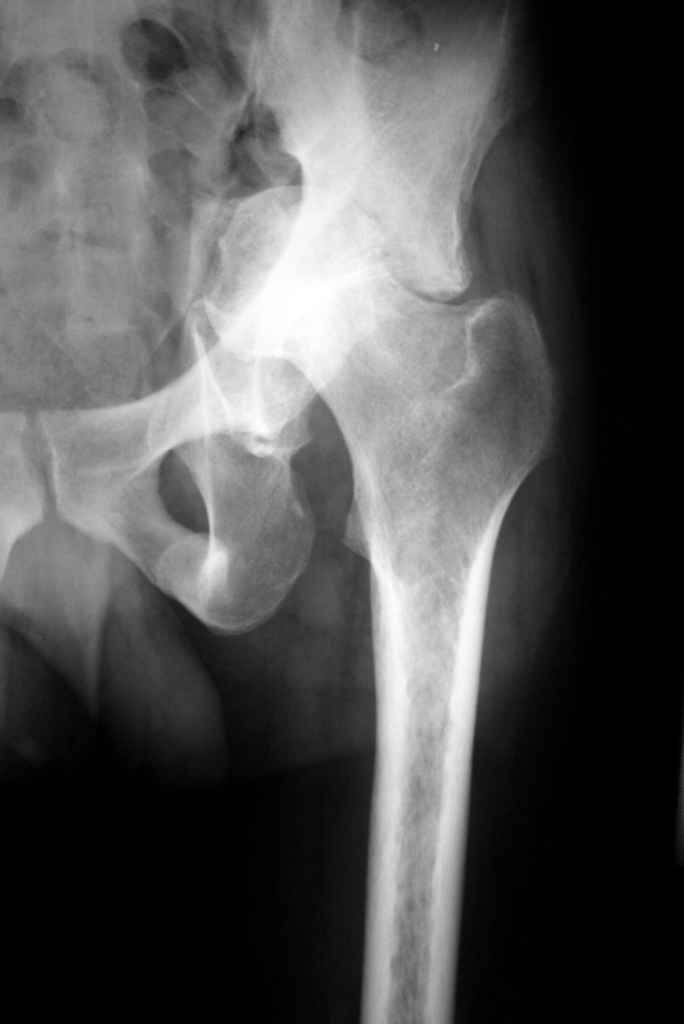

К сожалению, нередкая ситуация, мы предпочитаем выполнять операцию одномоментно - пластика задне-верхнего дефекта крыши ВВ собственной

головкой, установка вертлужного компонента бесцементной фиксации с обязательной дополнительной фиксацией винтами. Проблема будет в

восстановлении длины ноги, опыт показывает, что более 3-х см одномоментно восстановить очень сложно, и даже для этого потребуется широкая мобилизация бедра. В одном из номеров ж-ла Ортопедия травматология России мы опубликовали наш подход и р-ты лечения у больных с последствиями перелома ВВ.

Прилагаю в качестве иллюстрации одну из последних операций.